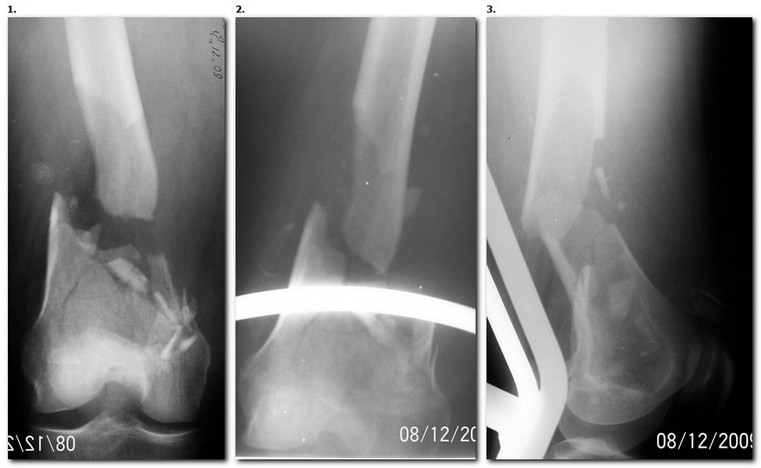

1. Открытый с дефектом кости 5 см оскольчатый внутрисуставной перелом дистального эпиметафиза бедренной кости. Величина дефекта установлена после сравнительных рентгенограмм обоих бёдер с линейкой. При поступлении выполнена ПХО раны, скелетное вытяжение за бугристость большеберцовой кости.

2. После долгих сомнений выполнена открытая репозиция перелома эпифиза бедренной кости, закрытый блокированный интрамедуллярный остеосинтез (к слову, оперативное вмешательство выполнено без применения ЭОПа). Предполагалась через 8 недель пластика костного дефекта спонгиозным аутотрансплантатом.

3. Снимок через 10 недель после операции. Имеется облаковидный регенерат. Решено от костной пластики воздержаться.

4. Через 6 месяцев имеем сросшийся перелом.